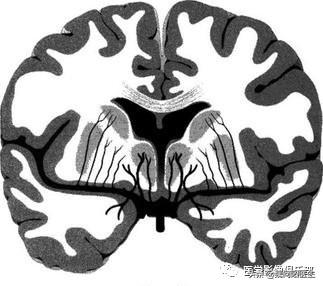

腔隙性脑梗死:是脑穿支小动脉闭塞引起的深部脑组织较小面积的缺血性坏死,一般<15mm圆形或椭圆形软化灶。好发部位为基底核区和丘脑区,也可发生于脑干、小脑等区域,单发或多发。不要轻视轻型脑梗死和TIA

腔隙性脑梗死是由于位于脑实质内穿支小动脉狭窄闭塞或微血栓形成导致局部缺血坏死;由于这些穿支小动脉的供血区域通常没有侧支循环,所以很容易发生缺血性梗死,

穿支动脉闭塞一般是建立在高血压病动脉硬化的基础上,常年高血压及血压波动状态,导致血管功能障碍,最后导致闭塞缺血坏死。